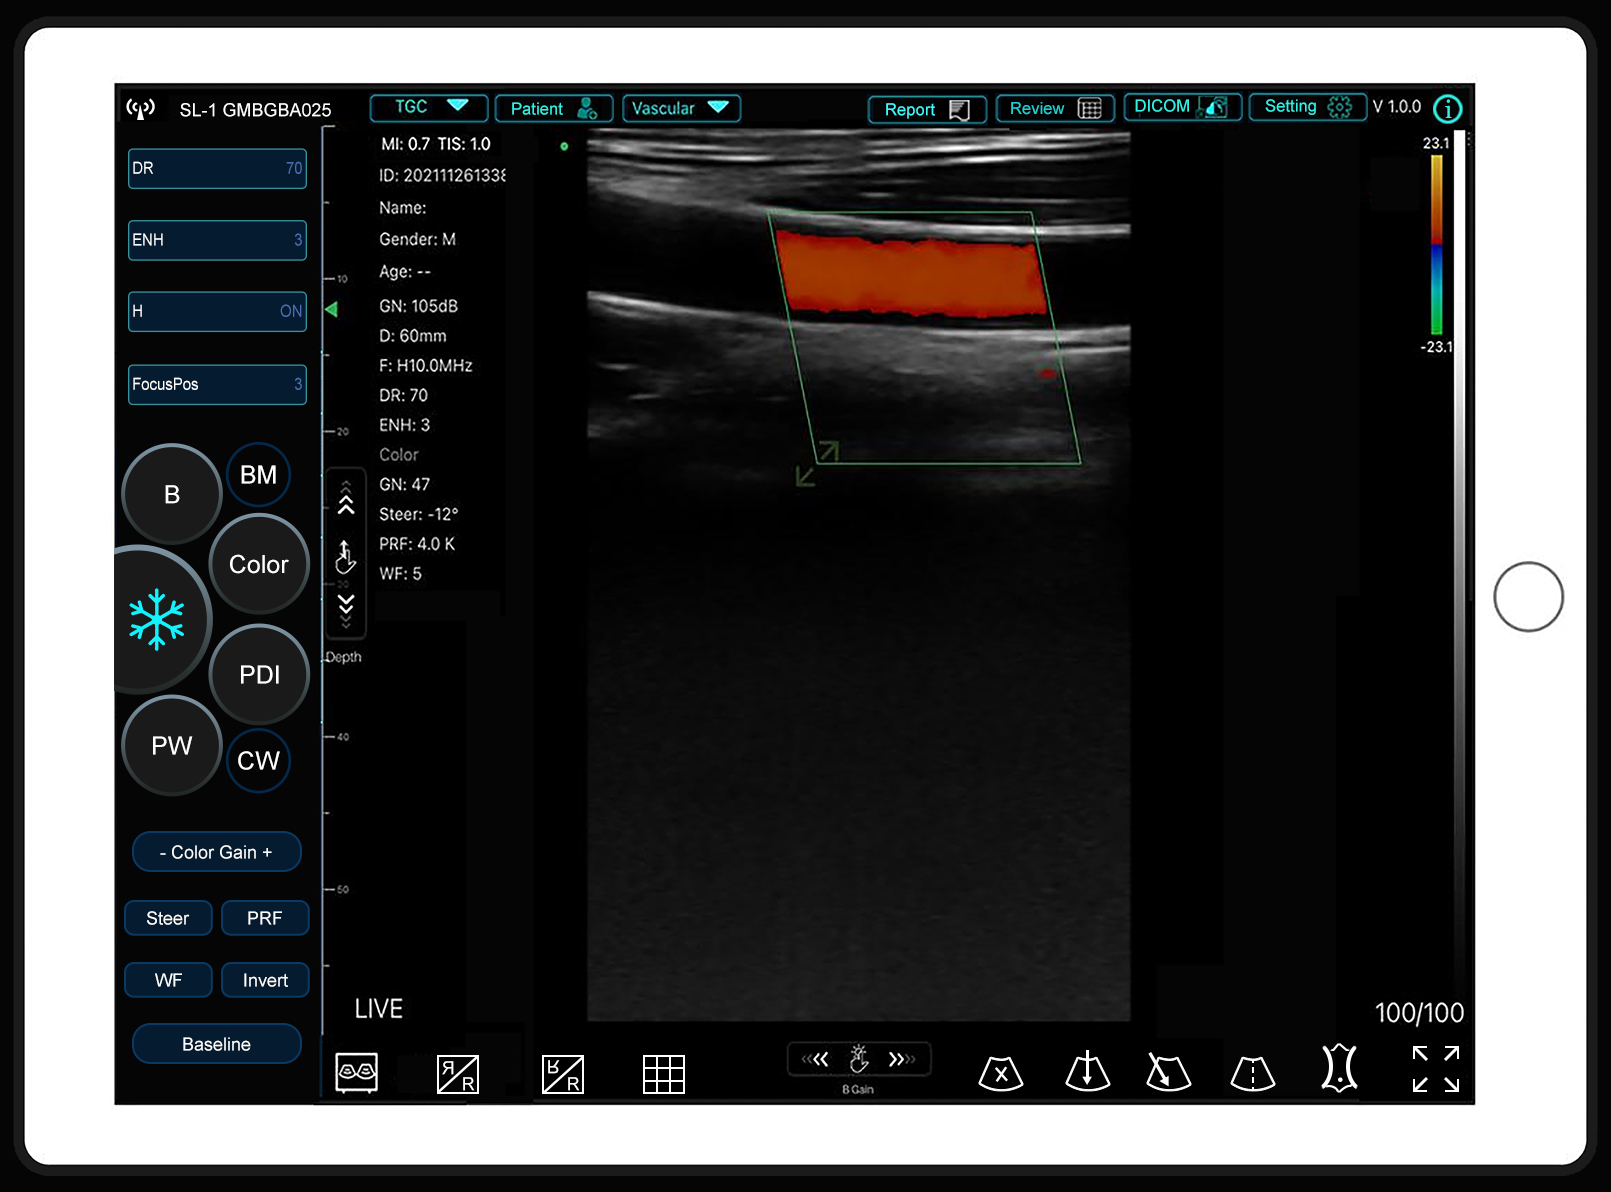

Sonostar has released a new APP called SmartUSG

Sonostar has released a new APP called SmartUSG.The interface of the new APP is more attractive andVIEW MORE →2026-03-18 -